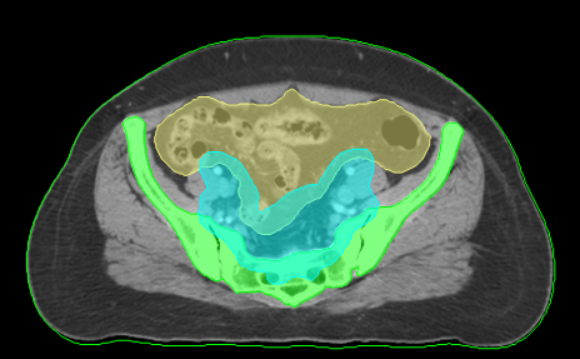

Cervix Challenge

3D-CRT